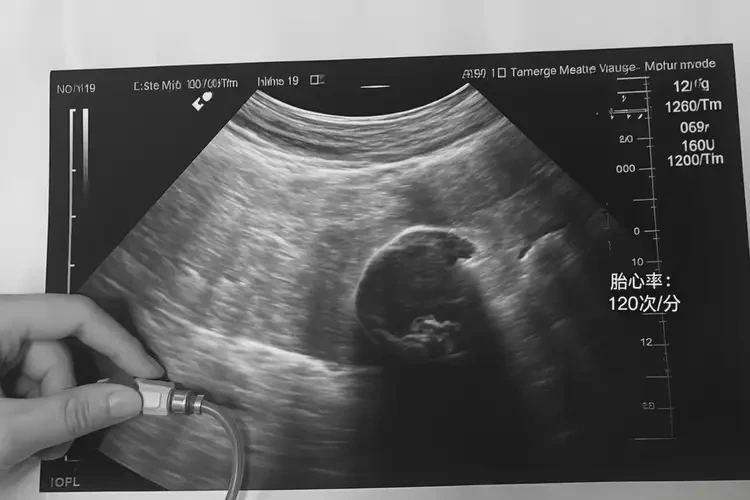

胎心100多次/分鐘

在孕4周2天時,胎心在100多次/分鐘是正?,F(xiàn)象。胎心是指胎兒的心跳,通常在懷孕6-8周時可以通過超聲波檢查到。在孕早期,胎心率通常在90-160次/分鐘之間波動,因此100多次/分鐘的胎心率在正常范圍內(nèi)。

孕4周2天胎心100多怎么回事(圖1)